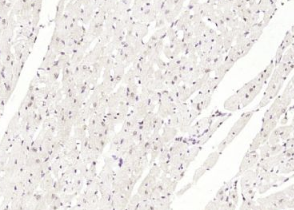

多聚甲醛固定,石蜡包埋(小鼠心脏);经柠檬酸钠缓冲液(pH6.0)煮沸15min后获得抗原;用3%过氧化氢阻断内源性过氧化物酶20分钟;阻断缓冲液(正常山羊血清)37℃30min;用(BNC1)多克隆抗体进行抗体孵育泰博体,未结合,1:400,4°C下过夜,然后根据SP试剂盒(兔子)说明和DAB染色进行操作。